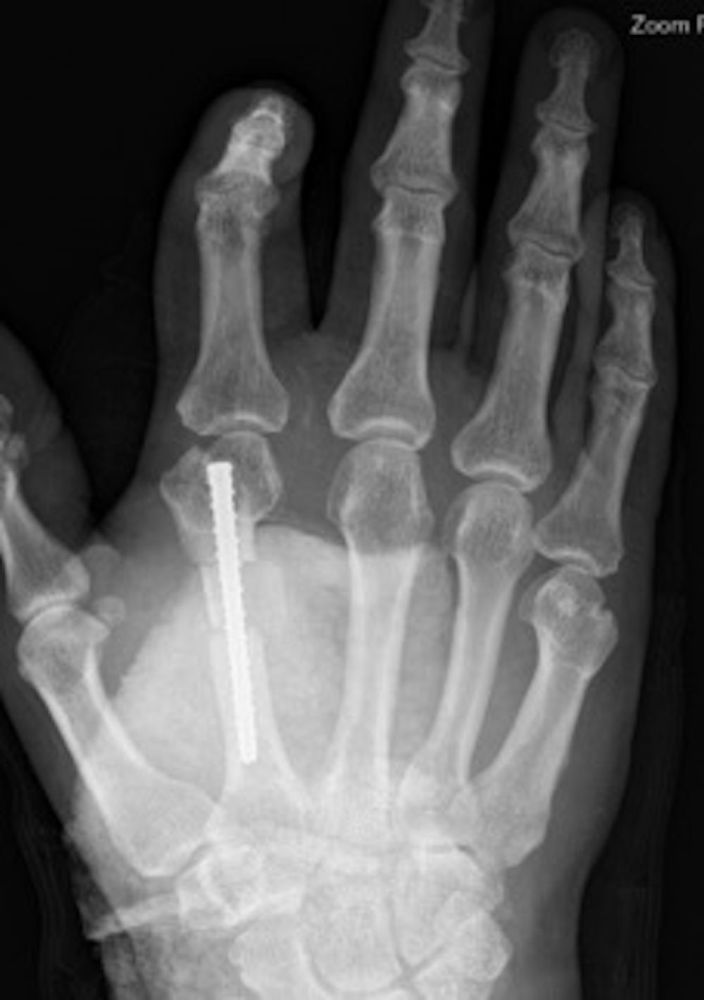

The graft was placed in the void over the guidewire and tamped into place to allow compression through the cortical interface. The metacarpal was then drilled in a cannulated fashion over the guidewire and a 4.5 × 50-mm headless noncompression screw was inserted while holding appropriate length, alignment, and rotation, and with graft in place (Figure 5). We recommend applying pressure over the graft as the screw is inserted to allow threads to engage without displacement. Final fluoroscopic imaging was obtained (Figures 6 and 7). At the conclusion of the case, length was restored and the patient had full passive range of motion. Standard closure was performed and the patient was placed into a volar blocking splint. The patient was instructed on hand elevation and allowed to work on active range of motion of the fingers.

Figure 5. Intraoperative posterior-anterior X-ray image of bone graft in place for metacarpal lengthening and compression screw being tightened.

Figure 6. Immediate postoperative posterior-anterior X-ray of cortical graft and compression screw in place.